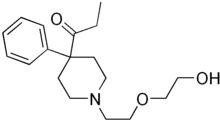

4-Phenylpiperidines

Pethidines (meperidines)

Structures